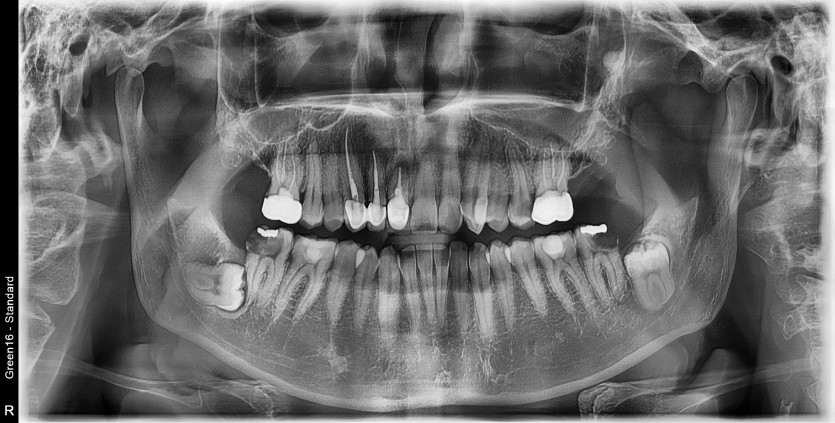

#38 사랑니 발치

구강 외과 전문의가 당일 발치했습니다.